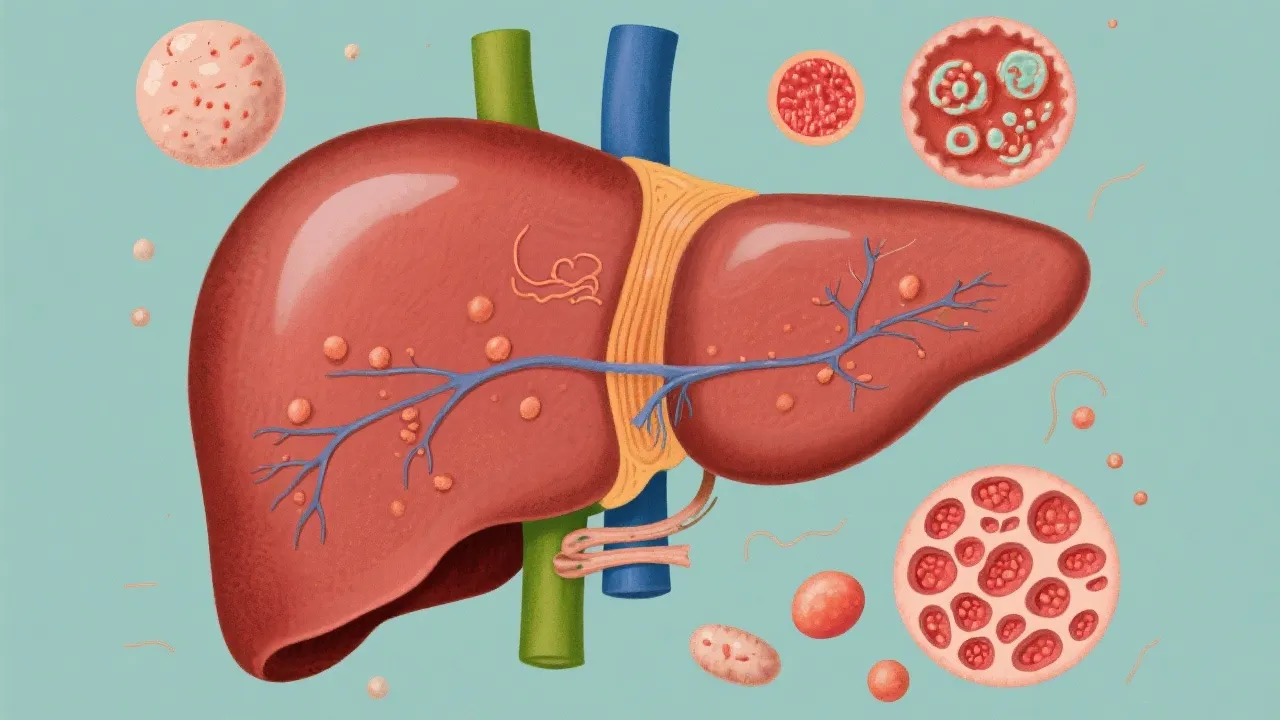

This article delves into the complex relationship between Non-Alcoholic Fatty Liver Disease (NAFLD) and Hepatocellular Carcinoma (HCC). NAFLD has emerged as a leading cause of liver diseases, often progressing without noticeable symptoms. Understanding this progression is crucial as it can lead to HCC, a primary liver cancer with significant health implications. Detailed insights on diagnosis, prevention, and treatment options are explored.

NAFLD is characterized by excessive fat accumulation in liver cells not caused by alcohol consumption. It encompasses a spectrum of liver conditions ranging from simple steatosis (fatty liver) to more severe forms such as non-alcoholic steatohepatitis (NASH), which involves liver inflammation and damage. NAFLD is becoming increasingly common worldwide, paralleling rising rates of obesity and metabolic syndromes.

The progression from NAFLD to HCC occurs through sequential stages, starting with liver inflammation and fibrosis. Over time, persistent liver damage can lead to cirrhosis, providing a fertile ground for the development of Hepatocellular Carcinoma. HCC remains one of the very common and deadliest forms of cancer globally, with high morbidity and mortality rates. This emphasizes the urgent need for early detection and intervention strategies.

The diagnosis of NAFLD and monitoring its progression to HCC involves a combination of imaging techniques, liver function tests, and sometimes, liver biopsy. While NAFLD itself may not initially show symptoms, risk factors such as obesity, diabetes, and metabolic disorders increase the likelihood of disease progression. Regular screenings for at-risk individuals are crucial.